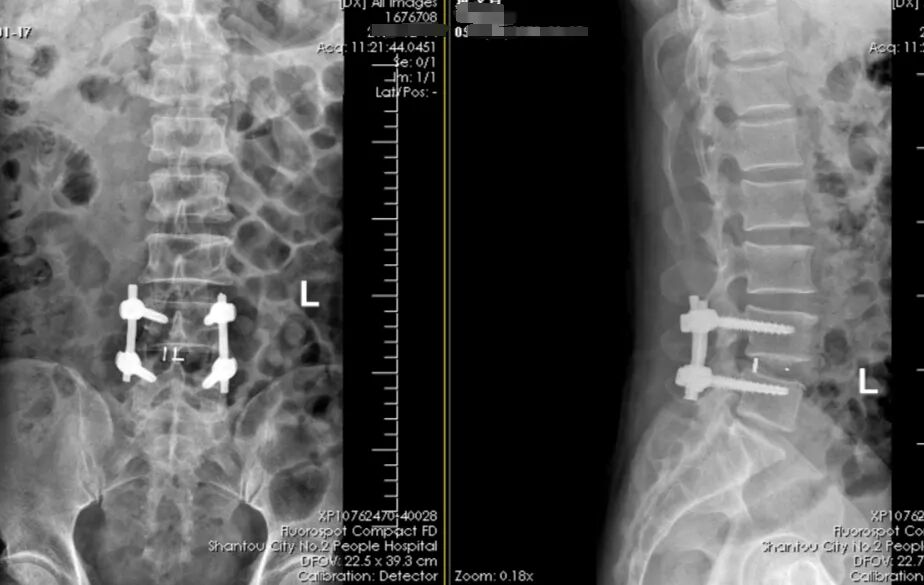

术后x光